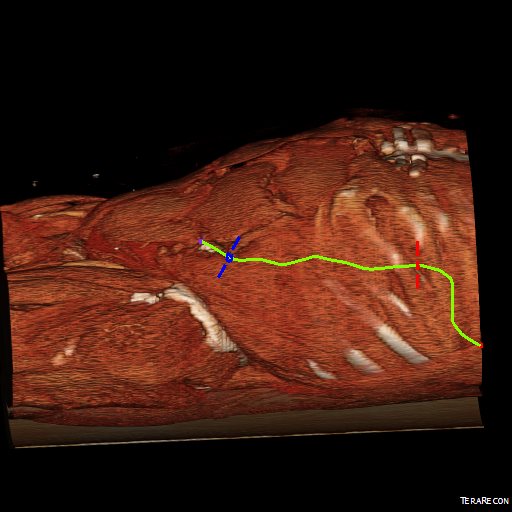

The patient was otherwise a healthy middle aged man with risk factors of smoking and hypertension. The centerline reconstructions showed the thoracic aorta above the aneurysm to be around 20mm in diameter and same below, with the celiac axis and superior mesenteric artery in the potential seal zone of a stent graft. The only plaque seen was around the level of the renal arteries and was focal and calcified. Looking at the list I had made as a comment to the Linked-In post, I realized that I really only had one viable option.

Open repair, usually the most expeditious option, was made challenging by the right hemothorax, making a left thoracotomy hazardous if the lung had to be deflated. Cardiopulmonary bypass would have to be arranged for, and that adds a metabolic hit that greatly raises the stakes. Of the endovascular solutions, the only viable option was TEVAR to exclude the rupture and debranching of the celiac axis and superior mesenteric artery. To those who would advocate for parallel grafts, there was no room in the normal 20mm diameter aorta. And branch systems for rupture are some time in the future. Also, the patient was becoming hypotensive. So the planned operation was first TEVAR to stop the bleeding, and then open surgical debranching. A hybrid repair.

The smallest stent graft we have is a 21mm graft, but it would not be suitable for this aorta. In practice, the normal aorta is quite elastic and will dilate much more than what is captured on a CTA. The next size we have is 28mm graft and I chose this to exclude the rupture, which was done percutaneously.